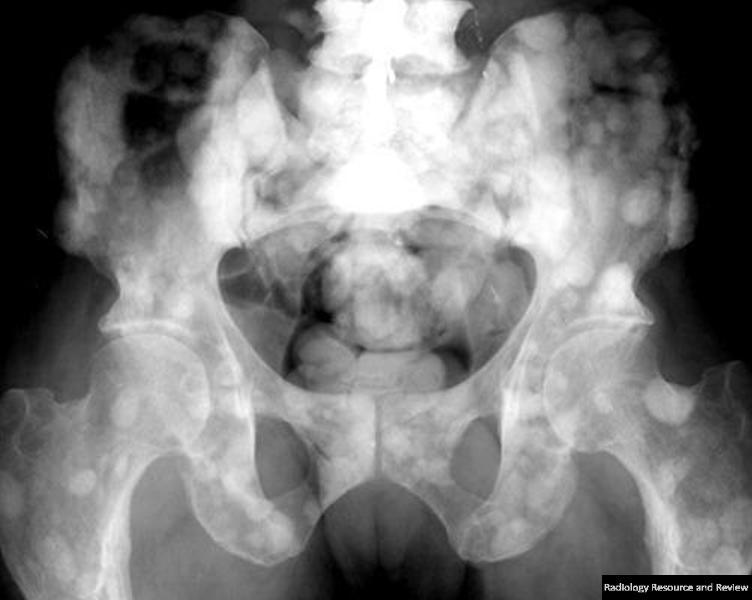

골 용해성 병변(Osteolytic)이 관찰된다면 : 신장암, 갑상선암, 위, 대장암 을 생각해 보아야 합니다.

(단발성 전이의 경우 신장암, 갑상선암에서는 전이 병소의 절제가 생존율 향상에 도움이 됩니다. 신장, 갑상선암은 혈관이 풍부하므로 선택적 동맥색전술을 예방적으로 하고 절제술을 하는 것이 안전합니다.)

조골성 병변(Osteoblastic)이 관찰된다면 : 전립선암, 방광암, 자궁암 을 생각해 보아야 하며

혼합성 병변이 관찰된다면 : 유방암 을 생각해보아야 합니다.

전이성 골종양의 경우 영상과 같이 치료가 무척 어렵습니다. 지푸라기라도 잡는 마음으로 방사선치료와 항암화학요법을 할 수 있습니다. 5년 생존율이 높아 보이는 환자군에서 장관골과 골반골의 임박 골절, 병적 골절 에는 예방적 고정술을 해볼 수 있습니다. (RT에도 효과가 없고, 2.5cm 정도로 큰 사이즈와 cortex가 50%이상 파괴되어 부러지기 직전일때, 소전자의 견열골절이 있을때 = Mirel 8점이상)